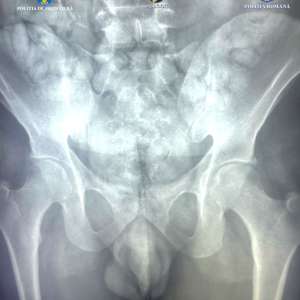

În urma controlului efectuat cu ajutorul unui scaner corporal cu raze X aflat în dotarea Poliției de Frontieră, în interiorul abdomenului inculpatului au fost observate mai multe formațiuni neobișnuite, care nu corespund anatomiei umane. În consecință, inculpatul a fost condus la o unitate spitalicească, unde, pe parcursul internării, a eliminat un număr de 62 de cașete, ce conțineau aproximativ 350 de grame de substanță pulverulentă (în prezent aflată în curs de expertizare).